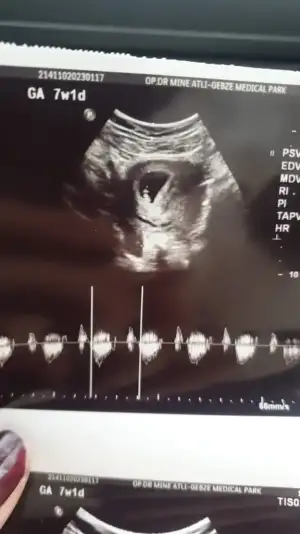

Kizlaaarr öncelikle Allah herkese bu duyguyu yaşatsın saglikla buyutsun bebelerini ben duydum bugün kalp atışını 6+6 haftalik dedi cok ritmik ve saglikli dedi cok şükür Allah'ıma cok mutluyum kizlarr🥰

Ayy maşallah maşallahhh 😍 şimdi buradaki atılan rahimin hangi konumunda tutunduguna göre cinsiyet tahmini diye bir fotoğraf vardi ya ? Ona göre sizinki erkek heheheh 🤭